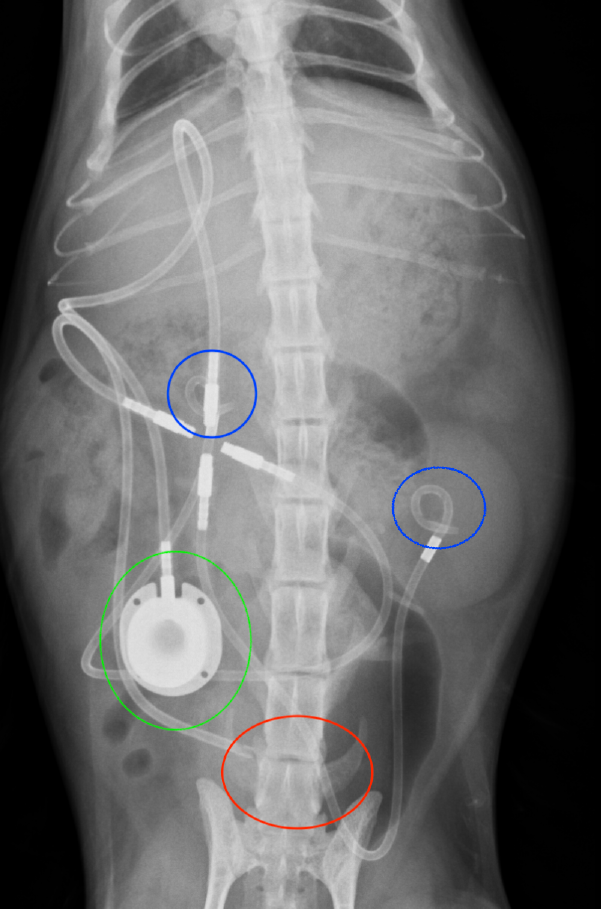

尿管の直上切開による摘出が難しい場合は、当院ではここ近年日本で行われるようになったSUB(Subcutaneous Ureteral Bypass)システムという腎臓から膀胱に人工バイパスを設置する手術を多く行っています。

術後の感染予防や、バイパスの石灰化を防ぐために定期的に来院して頂きバイパス内の洗浄を行う必要がありますが、バイパスの内腔が本来の尿管よりも太いことや、結石がバイパス内に閉塞しても、無麻酔で実施可能な洗浄をすることで開通する可能性があることもあり、尿管閉塞による急性腎不全の再発予防には非常に大きな効果があると言えます。何より内科療法でなかなか助けてあげれなかった命を助けてあげることができるので、非常に画期的な手術です。

※青丸は左右腎臓に挿入したSUBの一部。赤丸は膀胱に挿入したSUBの一部。緑丸は洗浄用の皮下のポートです。